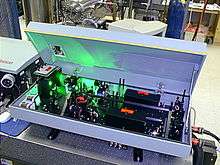

| Yttrium aluminium garnet laser (YAG laser) | to correct posterior capsular opacification (specially after removal of a cataract, if required), peripheral iridotomy, retinal surgery, laser-assisted sub-epithelial keratectomy (LASEK)[4] etc. |

NdYAG Laser